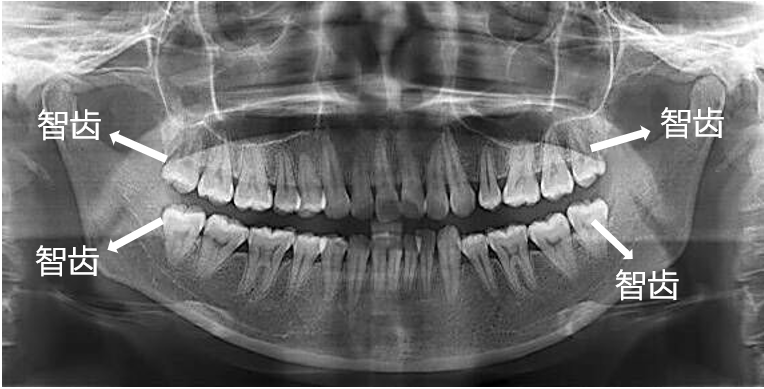

长歪的智齿,医学上称为阻生智齿。大多数阻生智齿要么完全埋伏在颌骨里,要靠X线片才能发现;要么“小荷才露尖尖角”,只冒出一点小牙尖。拔除这类智齿,周围的软、硬组织基本没啥变化,对瘦脸不会有丝毫作用。